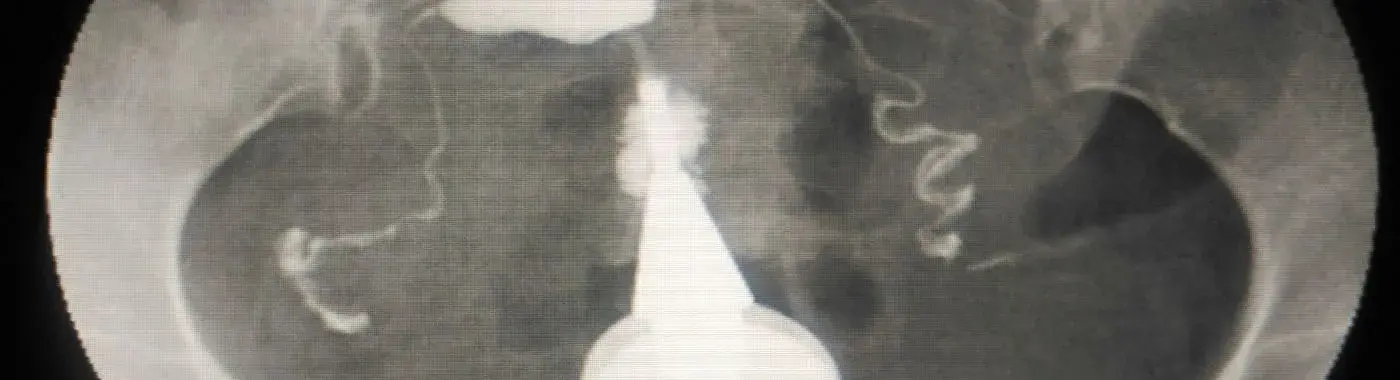

• Ultrasound: A pelvic ultrasound is a common imaging technique used to visualize the uterus and assess its position and any potential abnormalities.

• MRI: In some cases, magnetic resonance imaging (MRI) may be used for a more detailed view of the pelvic organs.